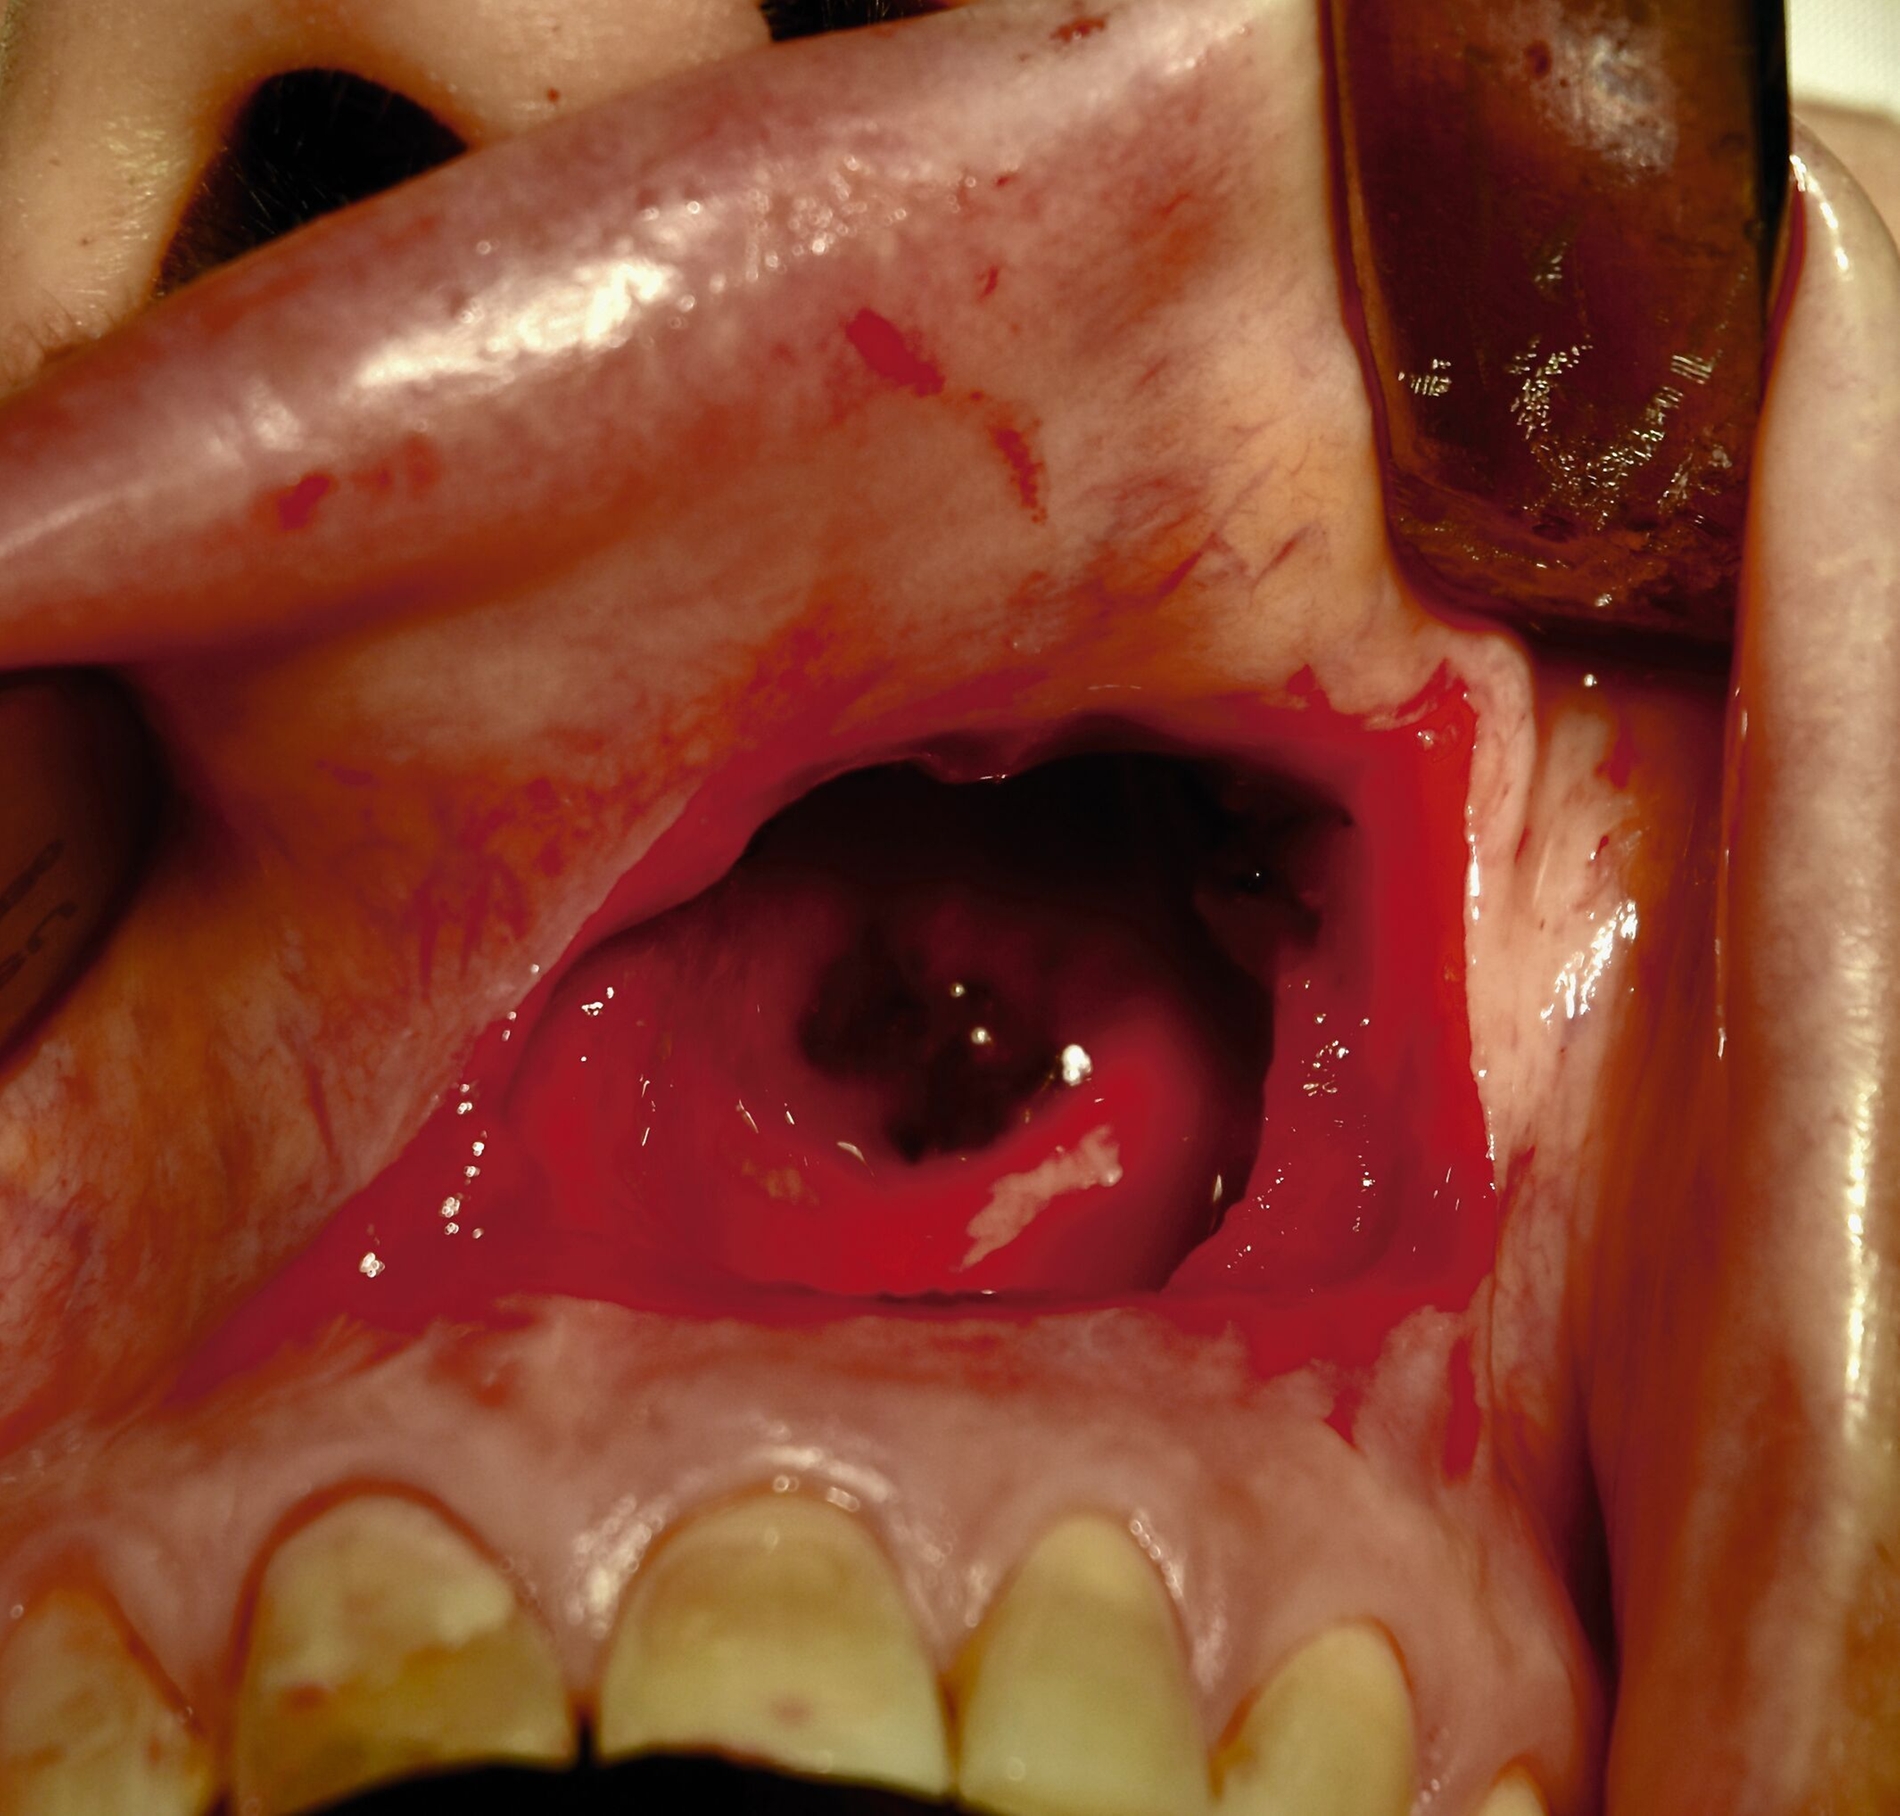

Die chirurgische Entfernung der zystischen Raumforderung gelang komplikationslos durch einen enoralen Zugang. Der Zystenbalg ließ sich einfach präparieren und von der knöchernen Umgebung gut abgrenzen. Der vorher abpunktierte Zysteninhalt war gelblich serös (Abbildungen 2a und 2c). Nach der Entfernung des Zystenbalgs bestand keine Exposition der Wurzelspitzen der Zähne 21 bis 24 (Abbildung 2b). Die Nasenschleimhaut konnte nach der Zystektomie vollständig und ohne Perforation erhalten werden.